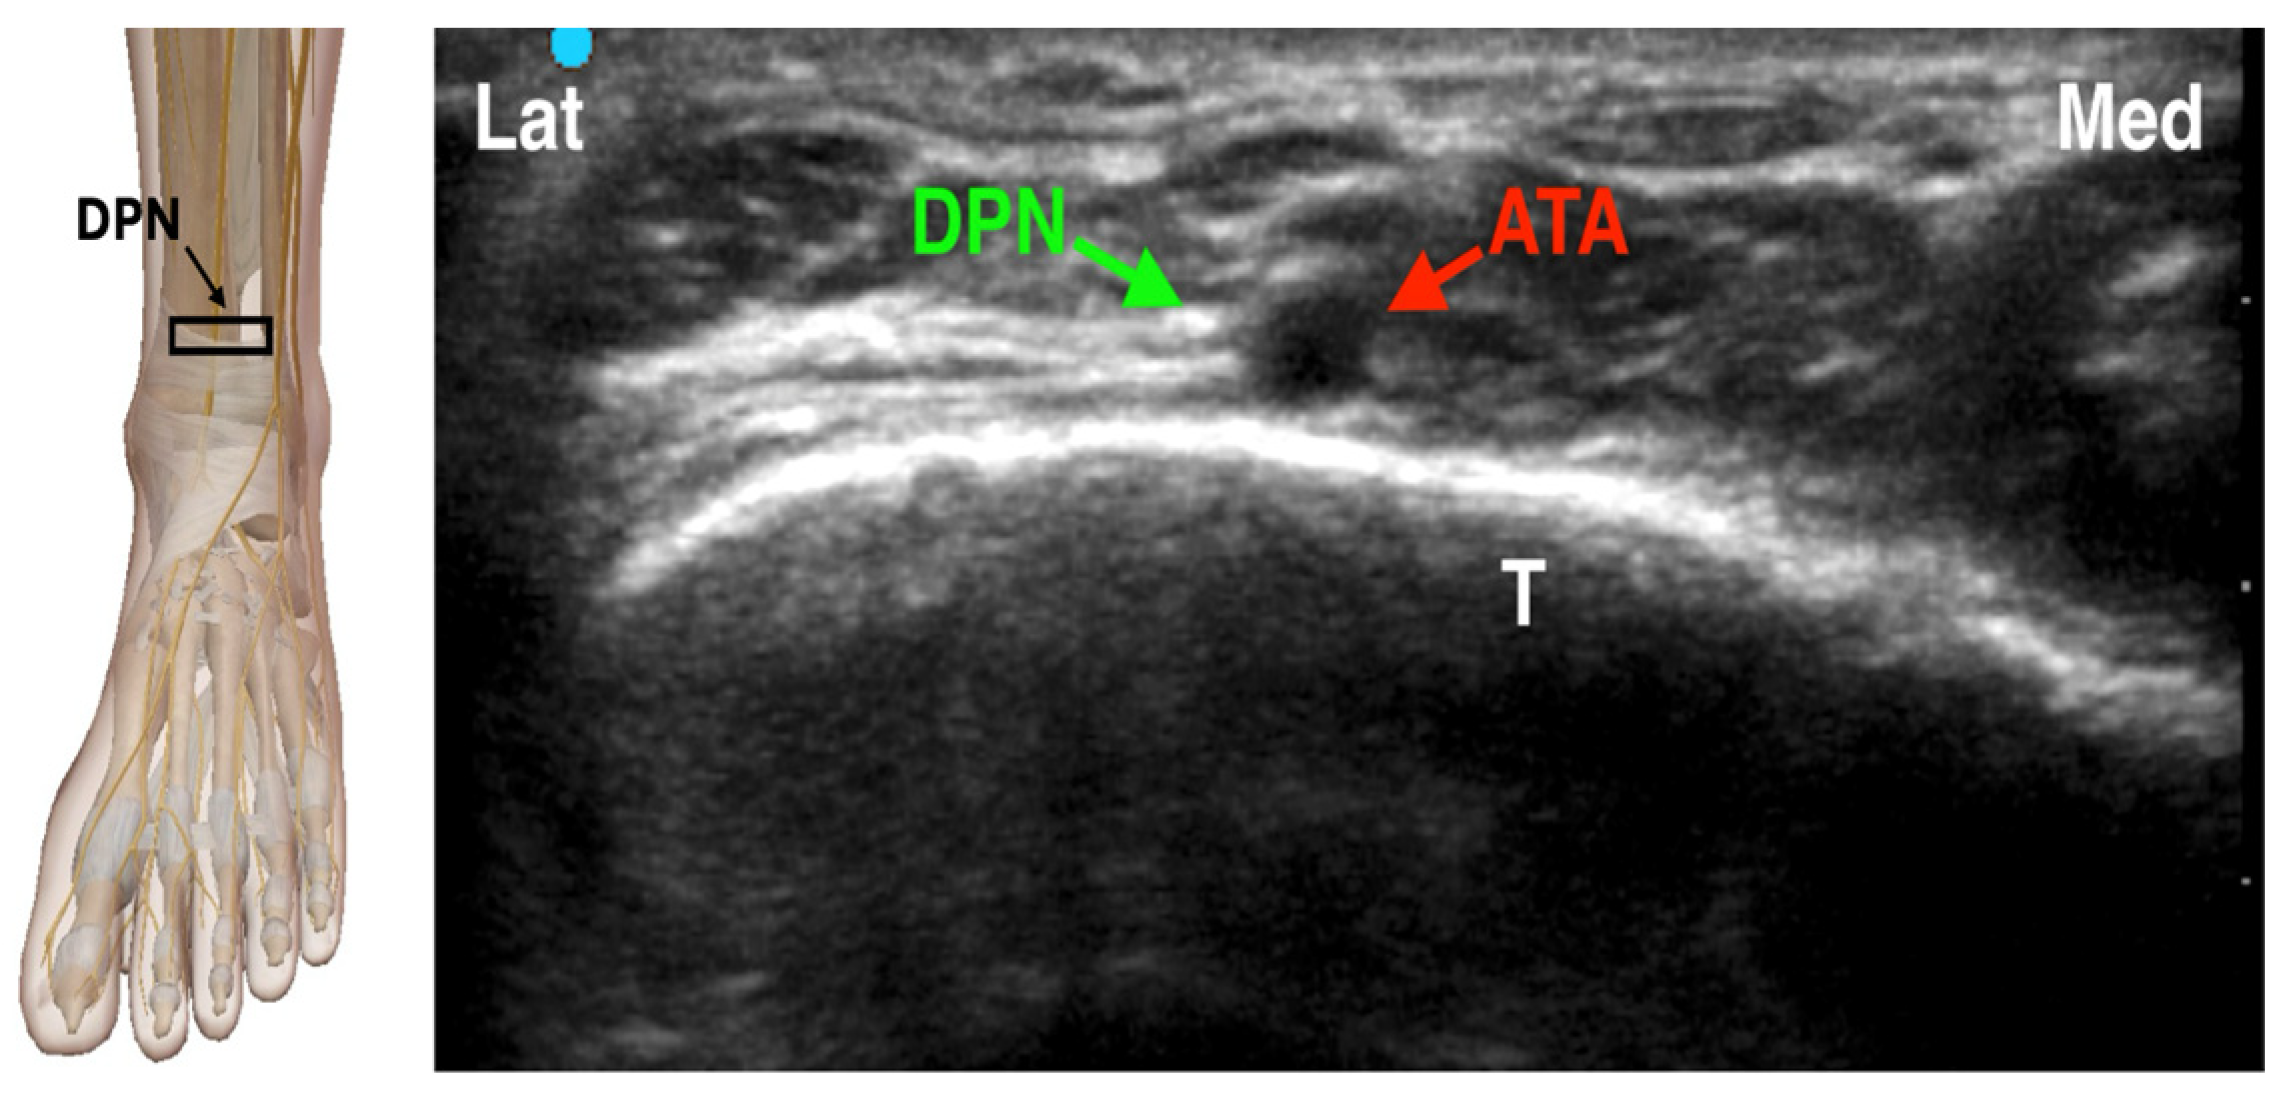

4.3.2. Deep Peroneal Nerve Block

The deep peroneal nerve provides motor innervation to the muscles of the anterior compartment of the leg and the extensor digitorum brevis, as well as sensory innervation to the first interdigital space between the hallux and second toe. It descends along the anterior tibial artery, medial to the interosseous membrane and deep to the extensor retinaculum at the level of the ankle [26]. When performing an ultrasound-guided deep peroneal nerve block at the ankle, the nerve typically appears lateral or anterior to the anterior tibial artery (ATA), just superficial to the hyperechoic cortex of the distal tibia. Key anatomical landmarks include the tibialis anterior tendon medially and the extensor digitorum longus and extensor hallucis longus tendons laterally. Dynamic scanning facilitates identification by highlighting the nerve’s relative movement to adjacent structures and its characteristic speckled echotexture. In clinical practice, the ultrasound probe is placed transversely on the dorsum of the foot just proximal to the ankle joint. The DPN appears as a small hyperechoic structure adjacent to the ATA (Figure 4). Using an in-plane approach, a 22- to 25-gauge needle is advanced, and 2–3 mL of local anesthetic is deposited around the nerve to achieve effective blockade [19,27,28].

Figure 4. Ultrasound-guided Deep peroneal Nerve Block. DPN: Deep Peroneal Nerve; ATA: Anterior Tibial Artery; T: Tibia. The black rectangle indicates the placement of the ultrasound probe on the anatomical area.